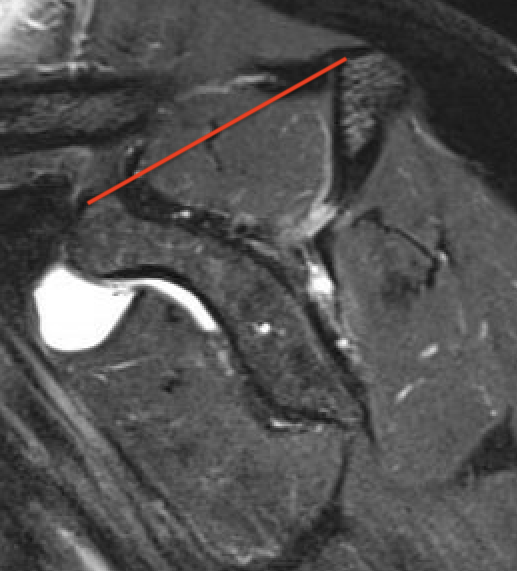

Supraspinatus atrophy

Tangent sign

- sagittal MRI

- line connecting superior coracoid and superior border scapular spine

- if supraspinatus muscle is below line, there is significant atrophy

- positive tangent sign / significant atrophy associated with larger tears / irrepairable tears

Negative tangent / no atrophy Positive tangent / significant supraspinatus atrophy